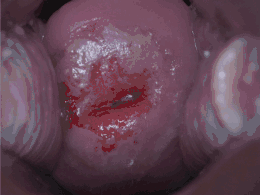

_normal_squamous_epithelium.jpg)

La NCI est classée en grades[14] :

| Grade histologique | Cytologie correspondante | Description | Image |

|---|---|---|---|

| 1 (catégorie I) | Lésion malpighienne intra-épithéliale de bas grade (LSIL) |

|

| 2/3 | Lésion malpighienne intra-épithéliale de haut grade (HSIL). |

| |

| 2 (grade II) |

| ![]() | |

| 3 (grade III) |

| ![]() |